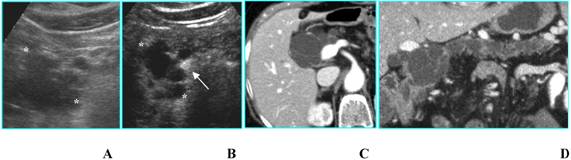

Nonfunctioning islet cell tumor in an asymptomatic 80-year-old woman. A. B-mode US shows a 2-cm hypoechoic nodule (calipers) located in the uncinate process of the pancreas. B. On CEUS the nodule is hyperechoic (asterisks) in the portal phase. C. Axial CT image depicts the same nodule as hyperdense in the venous phase (arrow).

Int J Med Sci Image

b) Islet cell tumors- functioning or nonfunctioning – are usually hyperechoic in the arterial phase (enhancement superior to normal pancreatic parenchyma) because of their rich vascularization [8]; after the enhancement a rapid washout of the lesion is appreciable, resulting in a slightly hypoechoic appearance during the venous phase [8]. Sometimes, enhancement is more important in the portal phase (Fig. 3), similarly to what has been reported for dynamic studies performed with CT [9]. In addition, in huge nonfunctioning islet cell tumors, enhancement may be heterogeneous due to necrosis or cystic degeneration [8].

A similar CEUS pattern can also be observed in hypervascular metastases (from renal cell carcinoma and melanoma) [3].